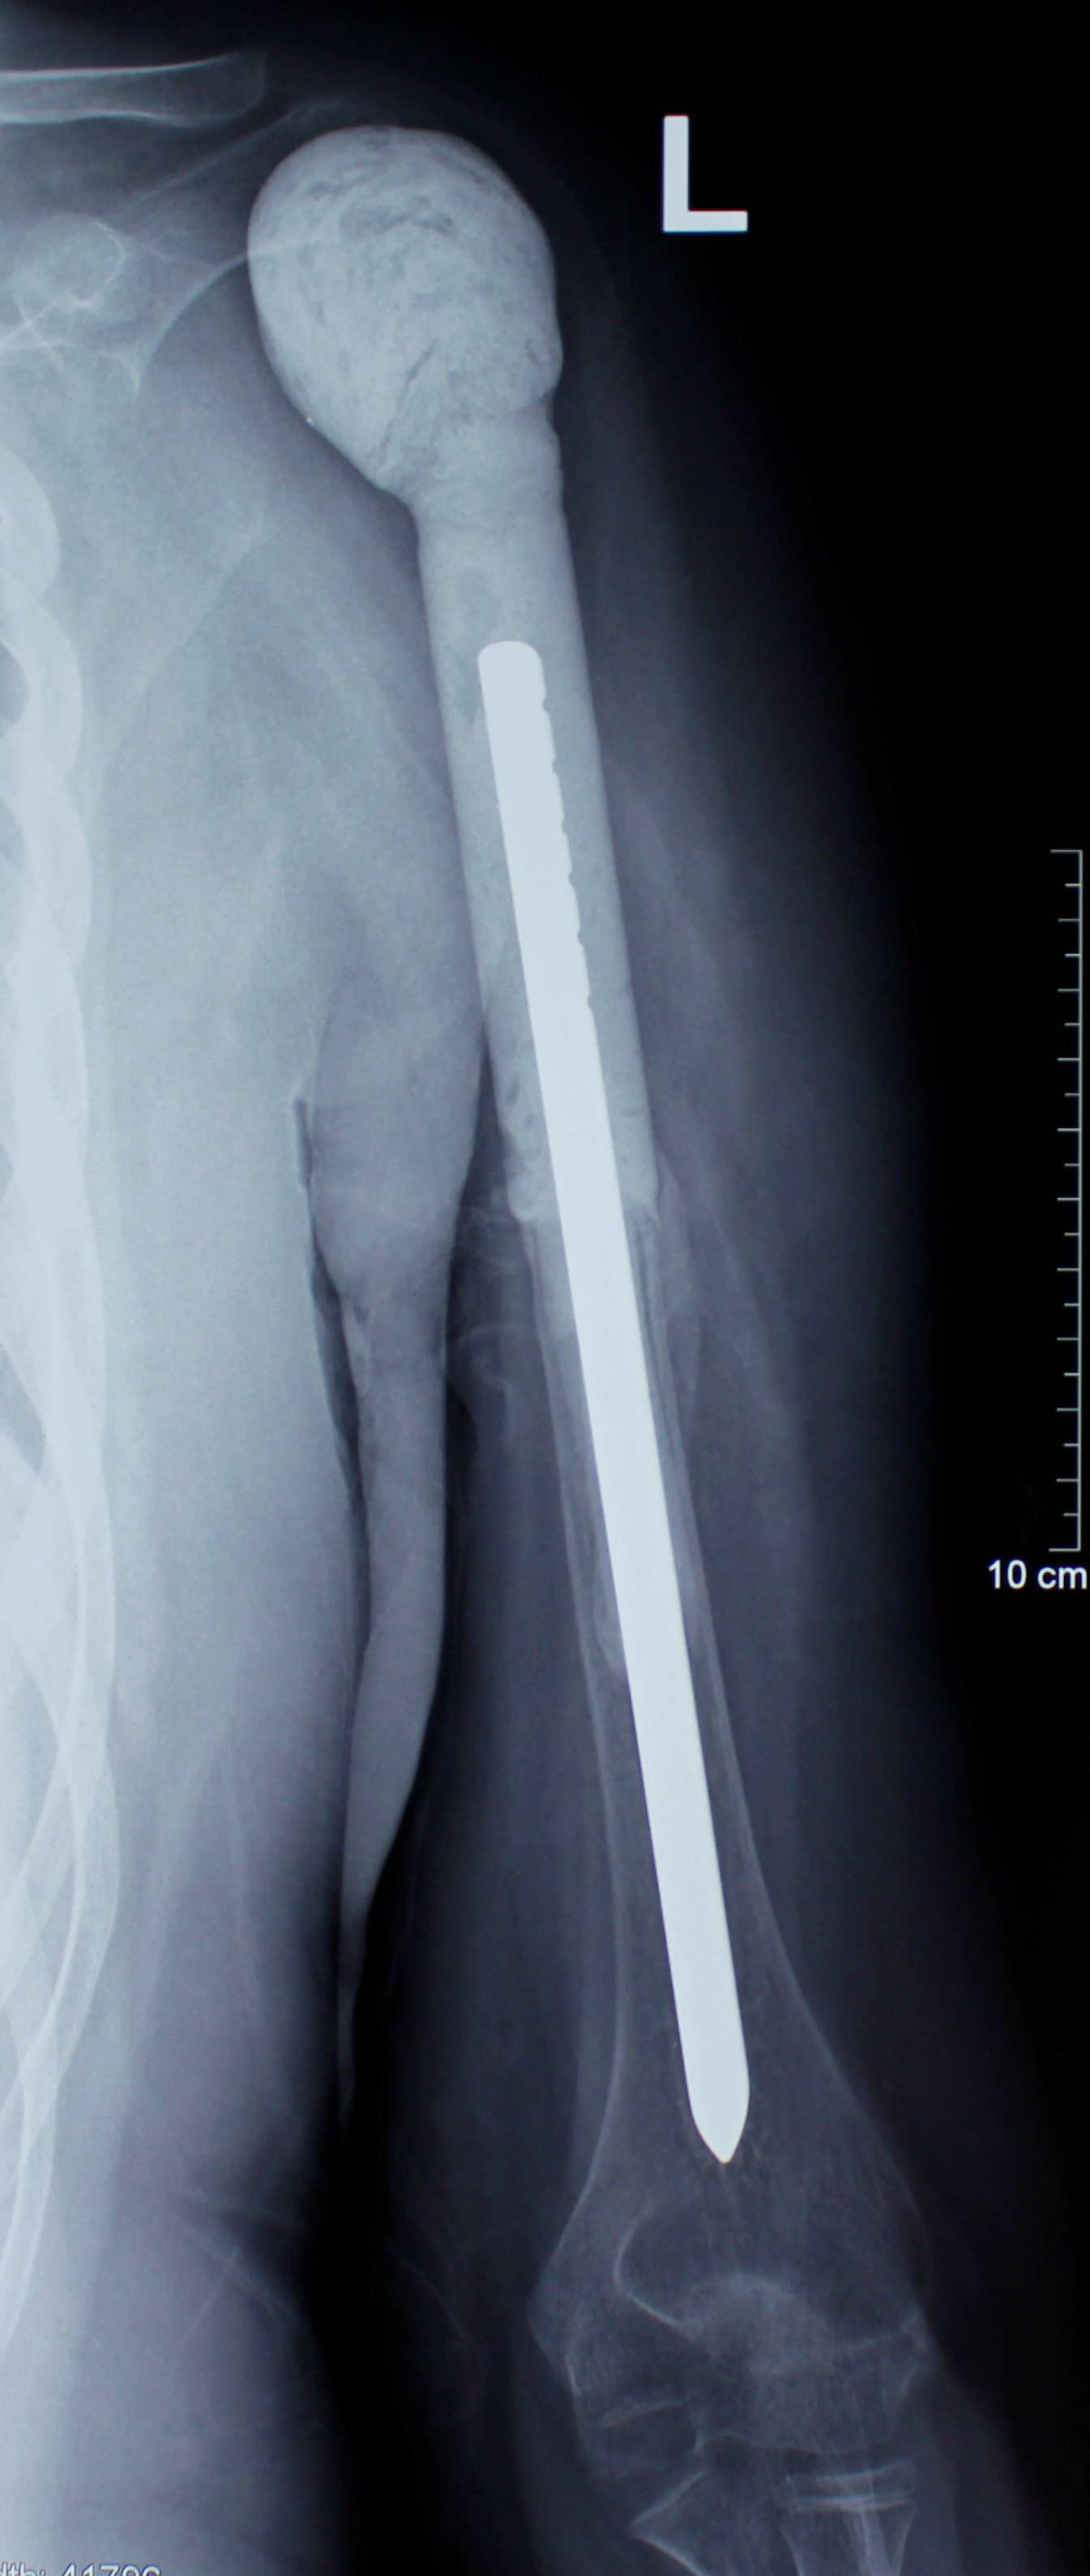

1 . ՌԴ-ում երկրորդային բնույթի կոտրվածքի ֆիքսացիա իրականացնելուց հետո՝ 40-ամյա բուժառուն դիմել է «Նաիրի» ԲԿ։ Բուժառուի մոտ ախտորոշվել է ոսկրային պլազմոցիտոմա։ Քիմոթերապիա ստանալուց հետո՝ 40-ամյա բուժառուն վիրահատվել է։ Կոնք-ազդրային հոդի հետ միասին հեռացվել է ազդրոսկրի վերին երրորդականը։ Առաջացած դեֆորմացիան շտկվել է էնդոպրոթեզով: «Նաիրի» ԲԿ-ի փորձառու թիմի և պրոֆեսիոնալ մոտեցման շնորհիվ՝ հաջողվել է պահպանել բուժառուի գործող վերջույթը։

Վիրահատությունից առաջ

Վիրահատությունից հետո